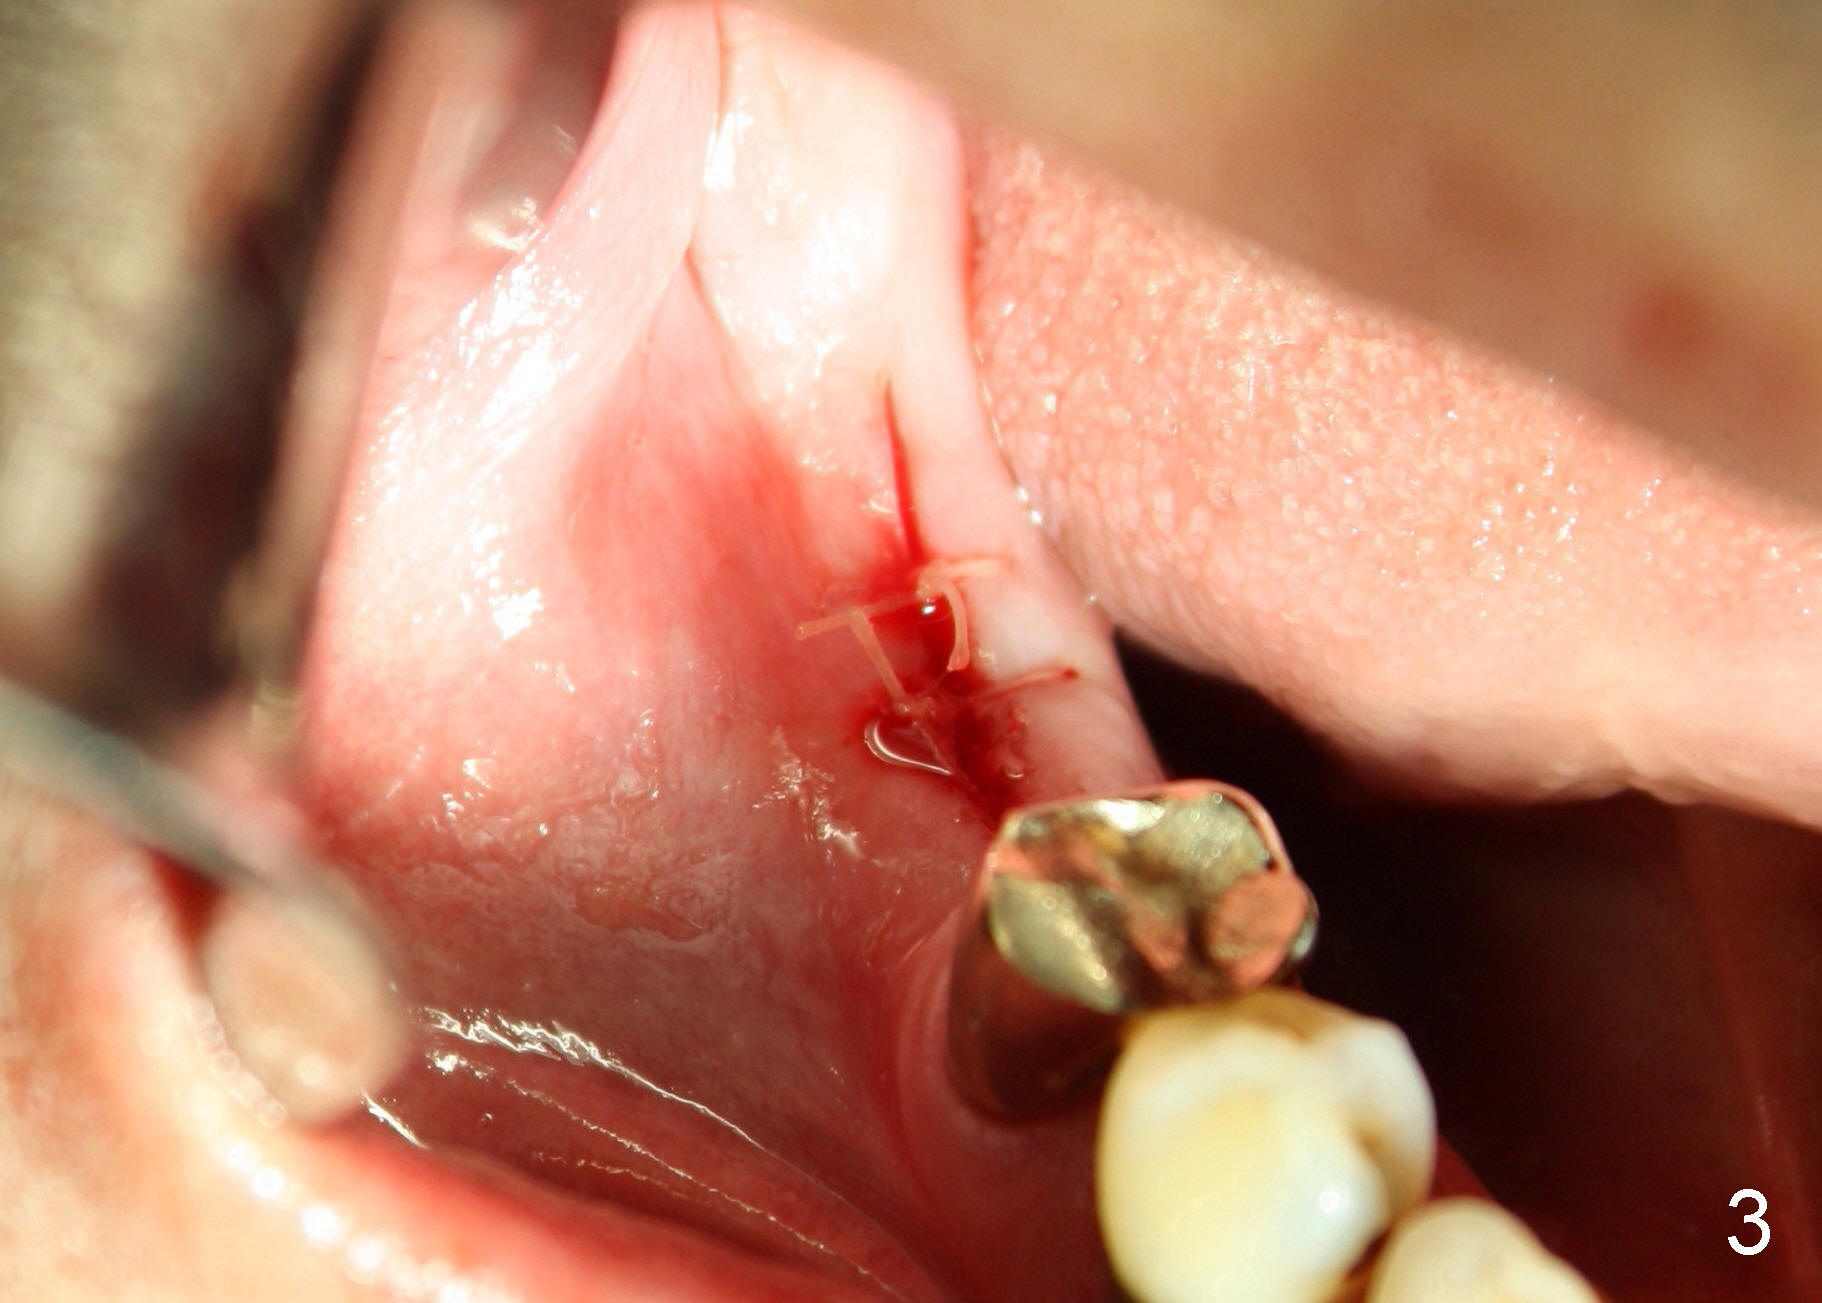

The second precaution to be taken to prevent post-implant infection is to place implant subgingival (submerged with suture to close the incision), instead of supragingival (Fig.3,4). Bicon 5x8 implant is used with bone expansion. The short implant also reduces chance of damage to the inferior alveolar nerve. Paresthesia and hyperethesia (pain) prevents the patient from keeping good oral hygiene post-operatively.

Postoperatively, there is minimal pain for Mr. Lip. The patient rinses with Chlorhexidine, although he does not take Amoxicillin. Luckily, there is no sign of infection either in #30 implant placement area (Fig.5, wound dehisces after suture removal), or in the extraction sockets (Fig.5'), one week postoperatively.